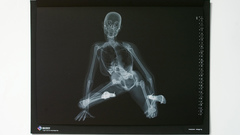

An X-ray, or X-radiation, is a penetrating form of high-energy electromagnetic radiation. Most X-rays have a wavelength ranging from 10 picometers to 10 nanometers, corresponding to frequencies in the range 30 petahertz to 30 exahertz (30×1015 Hz to 30×1018 Hz) and energies in the range 124 eV to 124 keV. X-ray wavelengths are shorter than those of UV rays and typically longer than those of gamma rays. In many languages, X-radiation is referred to as Röntgen radiation, after the German scientist Wilhelm Conrad Röntgen, who discovered it on November 8, 1895. He named it X-radiation to signify an unknown type of radiation. Spellings of X-ray(s) in English include the variants x-ray(s), xray(s), and X ray(s).